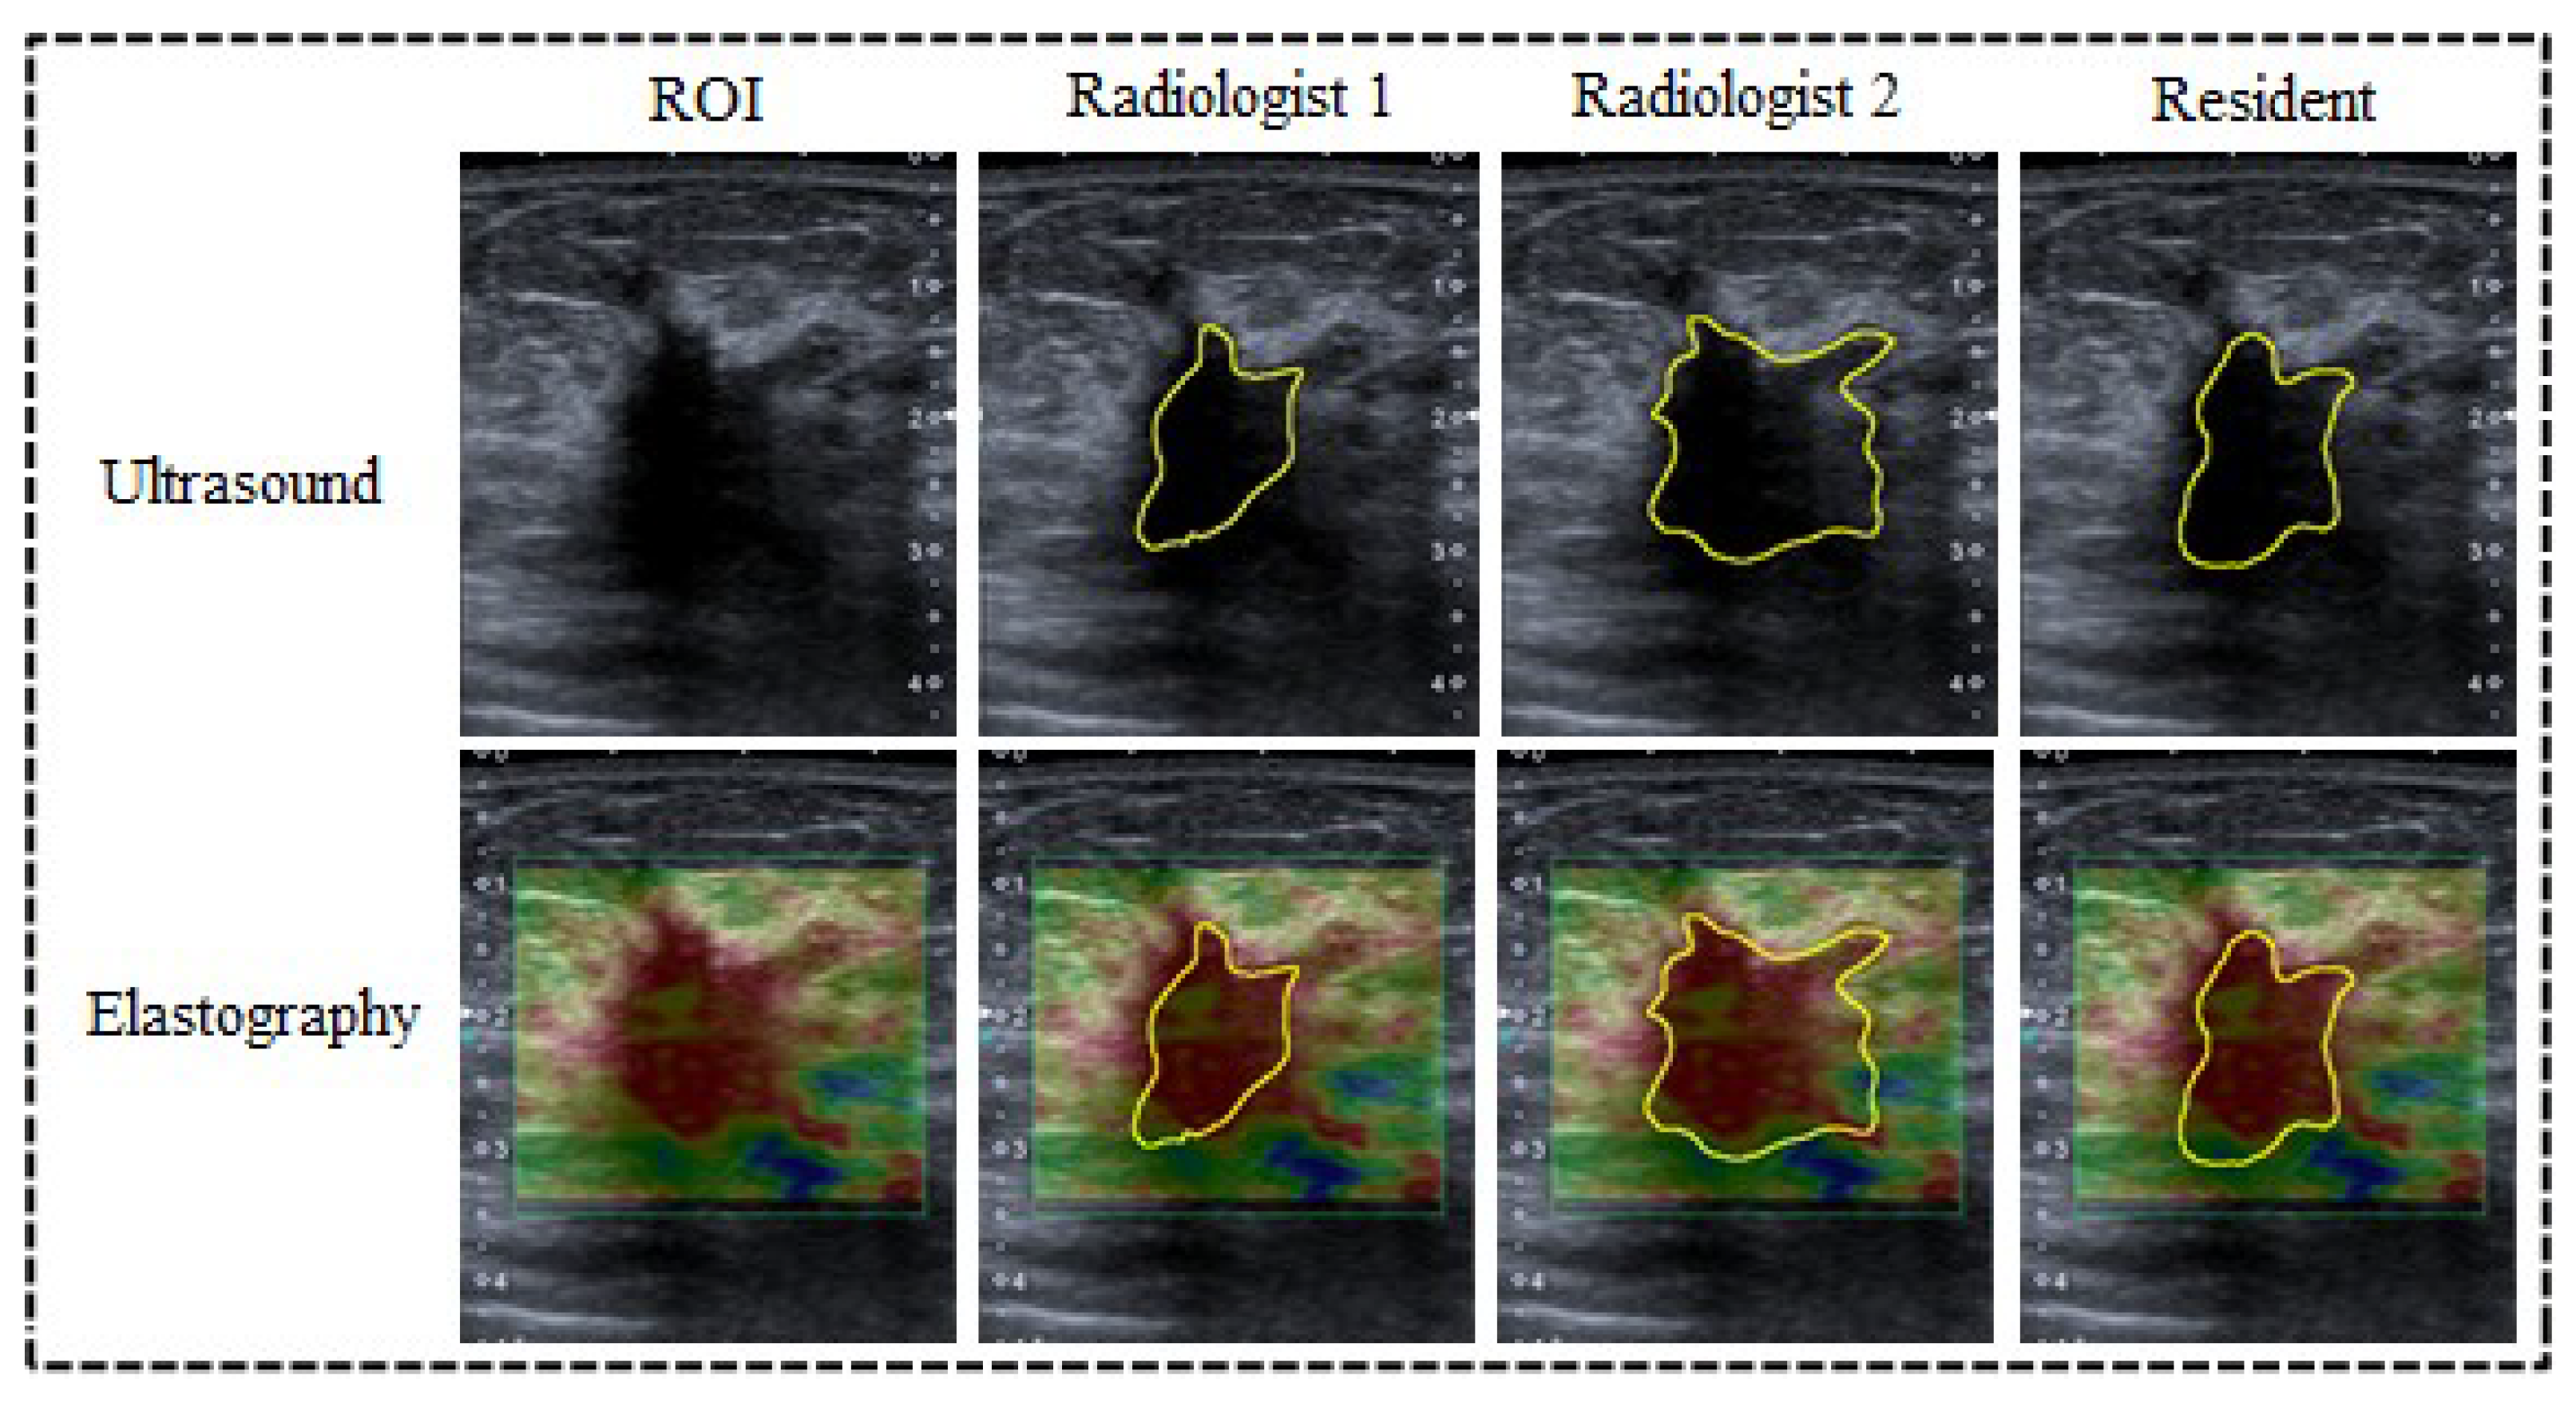

2.2. Delimitation of the Lesion